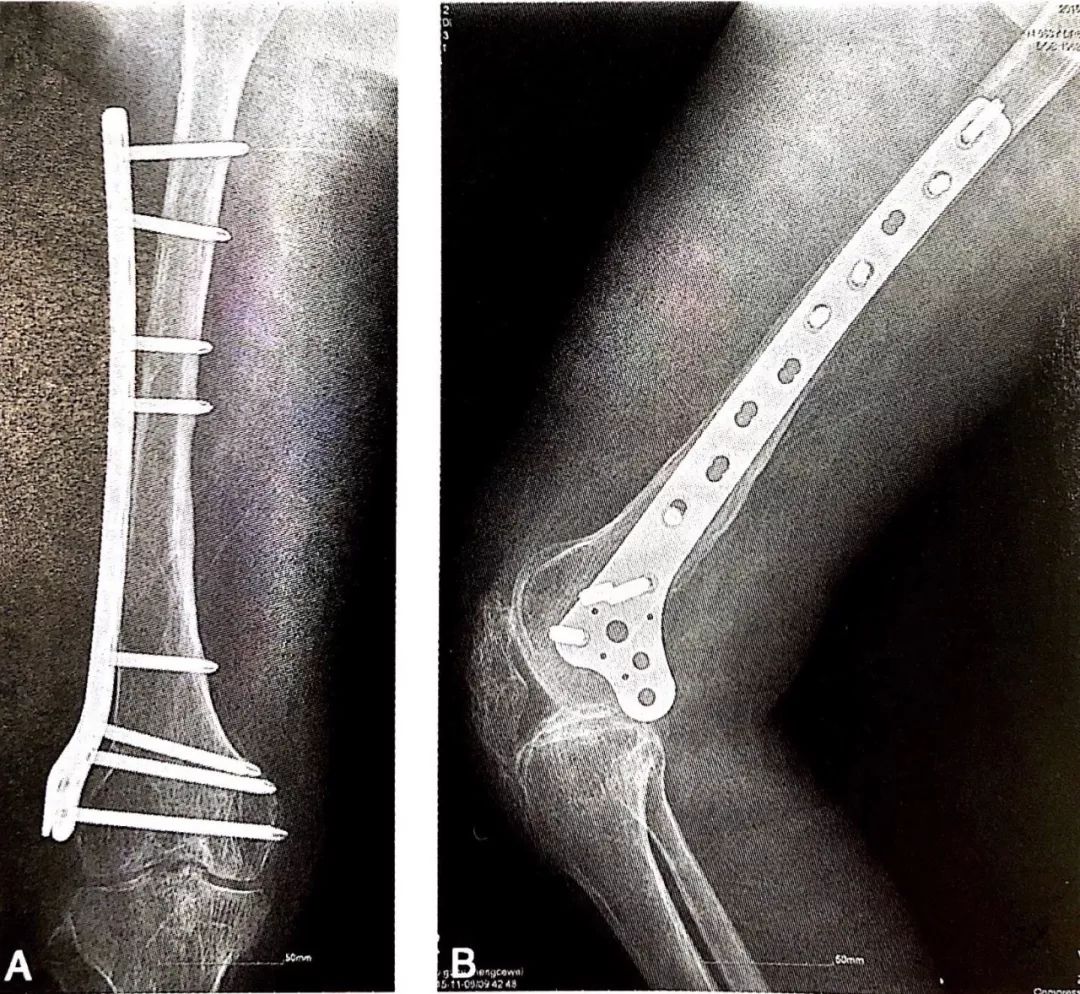

MIPO技术结合LCP内固定治疗四肢骨折术后一般需分期进行康复治疗。

股骨干骨折术后1年X线片:骨折愈合良好。

股骨干骨折术后1年外像:右膝关节屈曲达100°。

小切口取出接骨板,术后手法松解:右膝关节屈曲达130°,超过取板前30°。